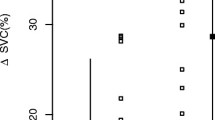

Thirty-one patients were men and nine were women, with an overall mean age of 63 ± 9 years (men: 65 ± 9, women: 63 ± 11). A total of 289 VLTs were administered but twenty-three VLTs preceded by vasopressor administration, were excluded. For the 266 remaining VLTs, the median number of VLTs per patient was 7 (range 3–8). The mean estimated blood loss was 1225 ml ± 305 ml. No patient received inotropic therapy during the study. All patients survived and no complication linked to hTEE usage has been highlighted. Table 1 summarizes the results of the haemodynamic measurements at baseline and after the VLTs. Of 266 VLTs studied, 243 (91%) were positive (≥ 11% increase in CI) and only 23 (9%) were negative (< 11% increase in CI) (Fig. 1). Among the 266 VLTs studied and the 243 +VLTs, we found a significant decrease from baseline to post VLT administration in both hSVC-CI and SVV. This was accompanied by a significant increase in CVP and CI (Table 1). Among the 23 negative VLTs the hSVC-CI, SVV, CVP and CI values did not change (Table 1). A comparison of variables measured at baseline between +VLTs and −VLTs showed significantly higher hSVC-CI (0.44 [0.39 to 0.51] vs. 0.35 [0.32 to 0.36] % P < 0.0001) and SVV (18.0 [16.0 to 21.0] vs. 13.0 [12.0 to 14.0] %; P < 0.0001) values and significantly lower CI (2.0 [1.8 to 2.2] vs. 2.5 [2.1 to 2.9] l min −1 m−2; P < 0.0001) values in +VLTs than in –VLTs (Table 1. Also, CVP values (10.0 [7.0 to 13.0] vs. 11.0 [6.0 to 14.0] mm Hg; P = 0.63) did not show any statistically significant difference between the +VLTs and –VLT groups (Table 1). Discrimination between +VLTs and −VLTs according to haemodynamic parameters was then evaluated by constructing ROC curves (Fig. 2). In the ROC curve analysis, both hSVC-CI and SVV showed good predictivity, with AUCs values of 0.92 (95% CI 0.88 to 0.95; P < 0.001) and 0.89 (95% CI 0.85 to 0.93; P < 0.001), respectively. No significant difference was found between the two AUCs (P = 0.56). The AUC for CVP (0.53, 95% CI 0.46 to 0.59; P = 0.69) was significantly lower than that for hSVC-CI and SVV, thus demonstrating poor predictivity for this parameter. The AUC for CVP was not significantly different from 0.5. Based on the Youden test, a baseline hSVC-CI cutoff value > 37% predicted fluid responsiveness with a sensitivity of 90% (95% CI: 86 to 94) and specificity of 83% (95% CI: 61 to 95). Baseline SVV cutoff values > 15% predicted fluid responsiveness with a sensitivity of 78% (95% CI: 72 to 82) and specificity of 100% (95% CI: 85 to 100).

Receiver operating characteristic curves describing the ability of hSVC-CI, SVV, and CVP to predict a fluid challenge-induced increase in cardiac index of at least 11%. hSVC-CI superior vena cava collapsibility measured with a miniaturized transoesophageal echocardiography probe, SVV stroke volume variation, CVP central venous pressure